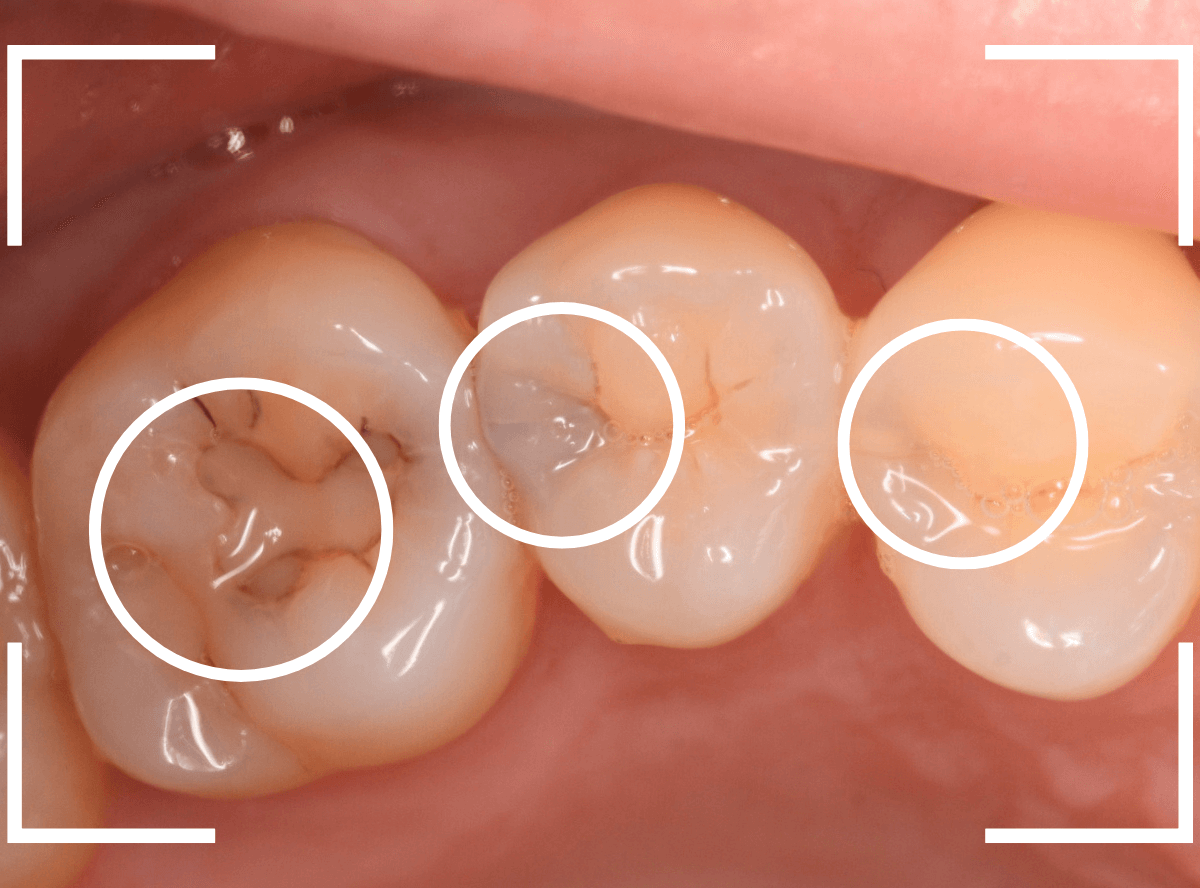

Case.8 大きな虫歯なのに、レントゲンではっきり写らない

こちらも定期検診希望で来院された患者さんです。

お口の中を拝見すると、明らかに虫歯がありました。

3本虫歯になっており、特に中央の小臼歯はかなり大きな虫歯になっているのが予想されます。

治療前にレントゲン写真で虫歯の大きさを確認するつもりが・・・あまりはっきり写ってきません。

患者さんに状況を説明して、歯を少しずつ削りながら虫歯を確認する事になりました。

まず、一番大きな虫歯と思われる部分を小さく削って確認します。

予想通り、虫歯が見えてきました。

隣りの奥歯と一緒に虫歯の治療を進めます。

色が染まっているところがまだ虫歯が残っている部分です。

2本とも、虫歯を全て取り切りました。

特に手前の歯はかなり広めの虫歯になっていました。

最終的に、手前の虫歯の除去も終わったところです。

手前の歯の虫歯は中央の歯まで達していました。

このように明らかに大きな虫歯があると診断されるような状況でも、レントゲン写真でうまく診断できない場合もあります。